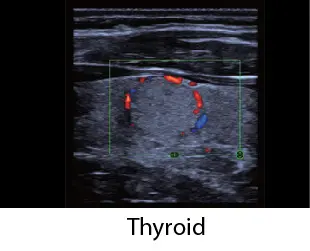

Чрез интегриране на множество приложения, TE Air e5M предлага сканиране на цялото тяло и се адаптира към различни клинични ситуации. Неговият безжичен дизайн осигурява възможност за извършване на ултразвукови изследвания с високо качество по всяко време и навсякъде. Освен своята универсалност, TE Air e5M предлага и редица интелигентни функции и обучителни инструменти, които повишават увереността и ефективността при работа.

Различни режими на визуализация: B-mode, M-mode, Color Doppler, Power Doppler, PW Doppler

Сканирайте цялото тяло с увереност

Абдомен, малки част, съдови, акушерство, гинекология, FAST и др

"как" и "какво" при извършване на ултразвукови изследвания. Включва анатомични илюстрации, стандартни ултразвукови изображения, референтни снимки за сканиране и съвети за умело извършване на диагностика. Обхваща приложения за корем, щитовидна жлеза, съдова система, малки части, урология, акушерство и гинекология, FAST протоколи, кардиология и нервна система.

Клинични снимки